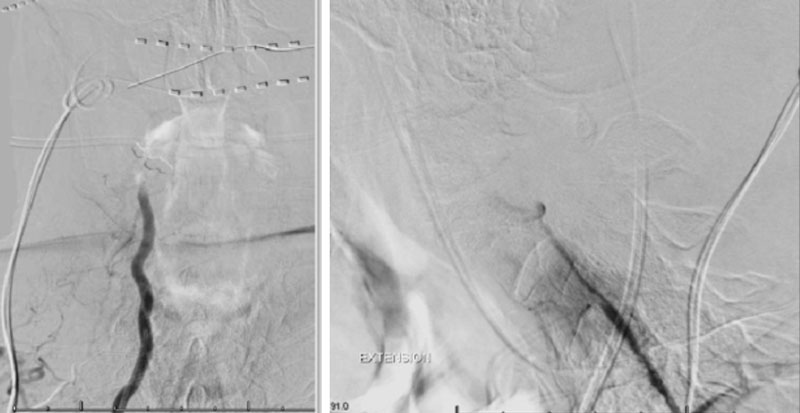

Dynamic provocative fluoroscopy failed to reveal significant Vertebral osseous instability (Figure 2A), however, Transcranial Doppler Flow velocities in the distal right Vertebral and Basilar Artery are markedly reduced during Extension of the Neck (Figure 2B).